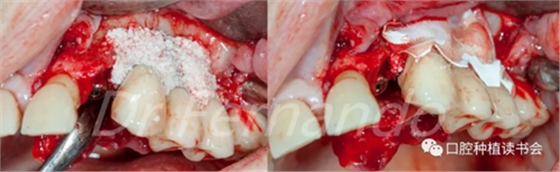

在無菌容器中將Cerasorb ?M(科盧森)骨粉與哌拉西林-他唑巴坦透明質(zhì)酸鈉溶液混合,將骨粉放置在缺損處,并用預(yù)先浸泡過哌拉西林-他唑巴坦透明質(zhì)酸鈉溶液的膠原膜覆蓋該區(qū)域并進行縫和(圖15、圖16 )。

圖15 種植體周圍骨缺損區(qū)植骨+覆蓋可吸收膜

然后根據(jù)種植體周圍炎的標準治療程序,先使用磷酸&氯己定凝膠處理種植體表面2分鐘后,接著使用抗生素溶液(透明質(zhì)酸鈉哌拉西林他唑巴坦)處理5分鐘,然后使用Cerasorb ?M 骨粉植骨(Curasan?-科盧森)(圖 21)。

圖21 機械&化學凈化種植體表面后,使用Cerasorb ?M 骨粉植骨

在骨粉上方覆蓋 Osgide? 可吸收膠原膜(Curasan?-科盧森) ,用絲線嚴密關(guān)閉傷口(圖 22 )

圖22 植骨區(qū)覆蓋可吸收膠原膜,關(guān)閉創(chuàng)口